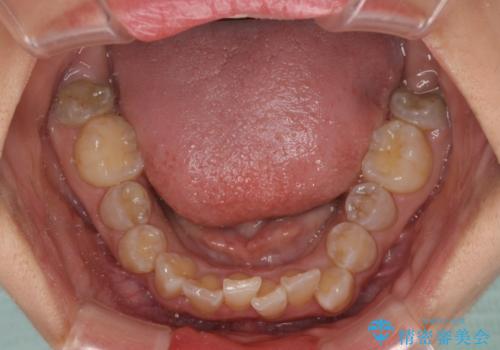

- 上下前歯のデコボコを気にして来院された患者様です。

上顎は両側の犬歯が骨内に埋伏しており、乳歯が残存している状態でした。

歯肉内に埋もれている場合には牽引することも可能ですが、両歯ともに骨内に完全に埋もれていたため、牽引することは不可能と判断しました。

口元の突出感があるわけではなく、叢生の程度もシビアではありませんでしたが、顎骨が小さく、左右ともに最後臼歯が歯肉に埋もれているため、下顎は左右第二小臼歯を抜歯することとしました。

上顎は左右ともに残存している乳歯を抜歯し、上下歯列を整えることとしました。